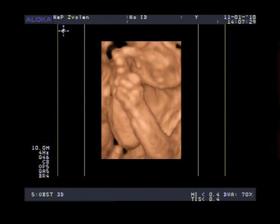

- 11.1.10 sme boli na 3D a pan doktor nam povedal ze to vyzera na DIEVČATKO 🙂